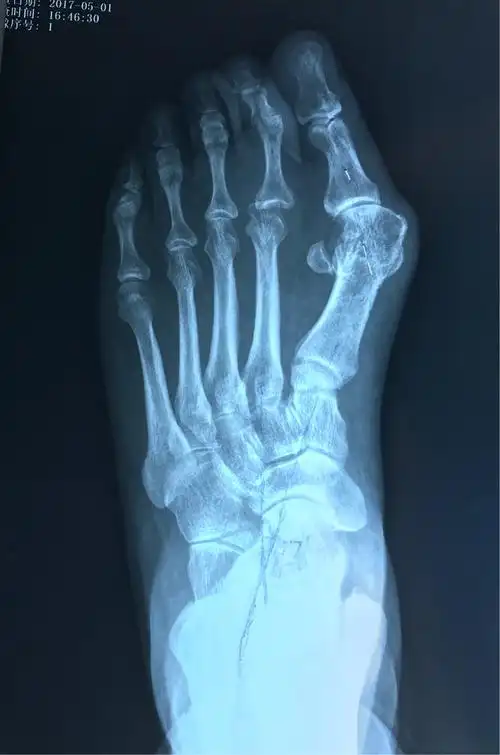

负重x线片观察:第一二跖骨间夹角增大明显,第二跖趾关节半脱位.

图片尺寸1200x1811